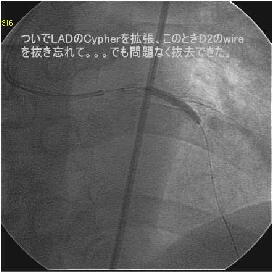

Crush���KBT.